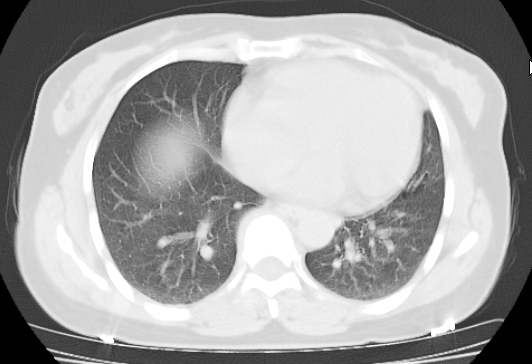

标题: CT25227:背部疼痛伴双侧胸壁痛2月,食欲差。 [打印本页]

标题: CT25227:背部疼痛伴双侧胸壁痛2月,食欲差。

肺结核并胸椎结核?请各位高手指教。

用椎体的条件来扫胸椎呀!考虑1左侧胸膜小结节形成2椎体结核并冷脓肿形成

左肺结核灶,胸椎结核并冷脓肿。

左肺结核灶,胸椎结核并冷脓肿